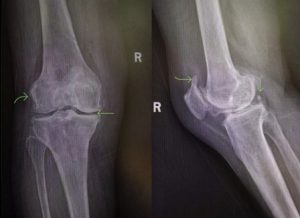

当您到医院就诊后,除了常规的“视、触、动、量”以外,医生一般会要求您拍摄一张x线片。x线是骨科疾病的最基本检查手段之一,也是骨关节炎影像学诊断的“金标准”。通常对于骨关节炎的影像学检查,往往无需ct、核磁共振(mri),一张简单的x线平片即可明确。当然,mri可显示关节软骨、半月板、交叉韧带、滑膜等关节软组织的情况,可以早期诊断和准确评价软组织的变性与损伤,是对x线检查的进一步补充。

这是膝关节骨关节炎典型的x线片,上图箭头所示右膝内侧间隙较外侧间隙明显狭窄,软骨下骨硬化;股骨、胫骨平台、髌骨上级边缘有增生的骨赘;侧位片显示关节后方有一枚关节内游离体。

图片引自骨关节炎诊疗指南(2021年版)